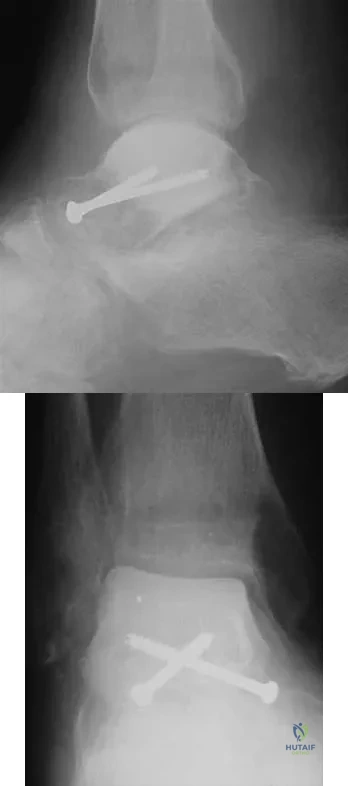

Question 34

A 28-year-old man who sustained an ankle fracture in a motor vehicle accident underwent open reduction and internal fixation 3 months ago. He continues to report significant ankle pain with ambulation. Radiographs are shown in Figure 26. What is the next most appropriate step in management?

Explanation